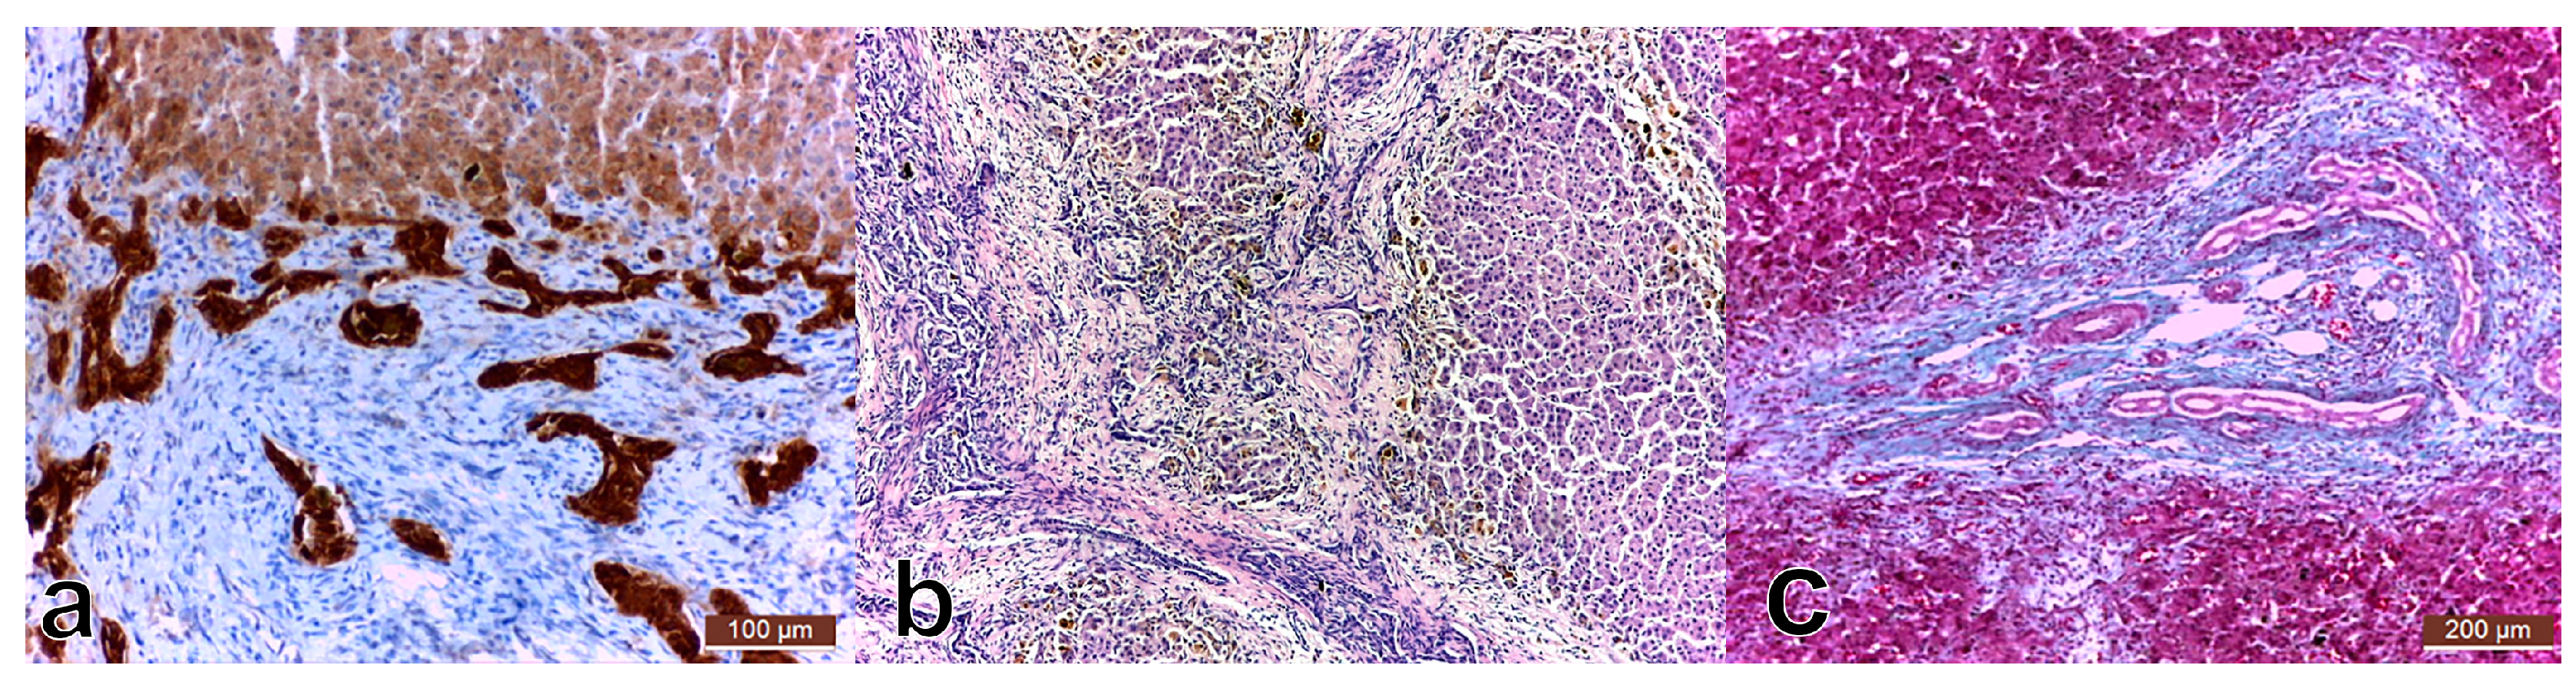

SMA was intensely positive on septa around the biliary neoducts. Some of the remaining normal liver lobules had veins, with sinusoids in which Ito stellate cells produced SMA, the cells being intensely positive. SMA positivity was also identified in Kupffer and endothelial cells with deposits in the Disse spaces; also, intensity for SMA in the capillaries was higher when they were closer to the confluence with the centro-lobular vein. In the portal structures, SMA was positive in the muscle layer of the arteries and the normal bile ducts (Figure 2).

Figure 2.

Smooth muscle actin (SMA) highly positive on the bridges around the neoformed bile ducts. Overall appearance 40×.

SMA is a useful immunohistochemical marker for the development of liver fibrosis and a predictive tool for early liver fibrogenesis in infants with biliary atresia. The hepatic expression is a histopathological marker for activated stellate cells responsible for liver fibrogenesis [19]. In our study, SMA was intensely positive in the bridges around neoducts, expressed by the Ito stellate cells, but also Kupffer and endothelial cells, as proof of advanced fibrosis.